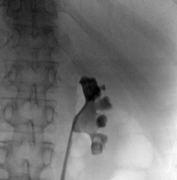

Prior to the procedure, a retrograde ureteral access catheter with extension tubing is placed. The patient is then placed in the prone position and the flank of interest is exposed. The fluoroscopic C-arm is rotated 30° cephalad to provide an adequate view of the calyx of interest.

The extension tubing is used to perform an intraoperative retrograde pyelogram. Distension of the calyces provides enhanced visibility during US access. A probe with an attached needle guide is used, and the needle is placed under direct vision into the calyx of interest. US access allows for real-time monitoring of the needle tip.

Confirmation of correct access is aided by fluoroscopic imaging, return of urine and guidewire placement. The guidewire is led all the way down the ureter. The needle is exchanged for a 6-Fr dilator, which is placed all the way past the ureteropelvic junction (UPJ), and the guidewire is exchanged for a super stiff wire. After confirmation the wire is at the level of the bladder, a sub-centimeter skin incision is made. Serial dilators are then used, dilating the fascia up to 14 Fr. A 16 or 18 Fr access sheath with suction capability is used.